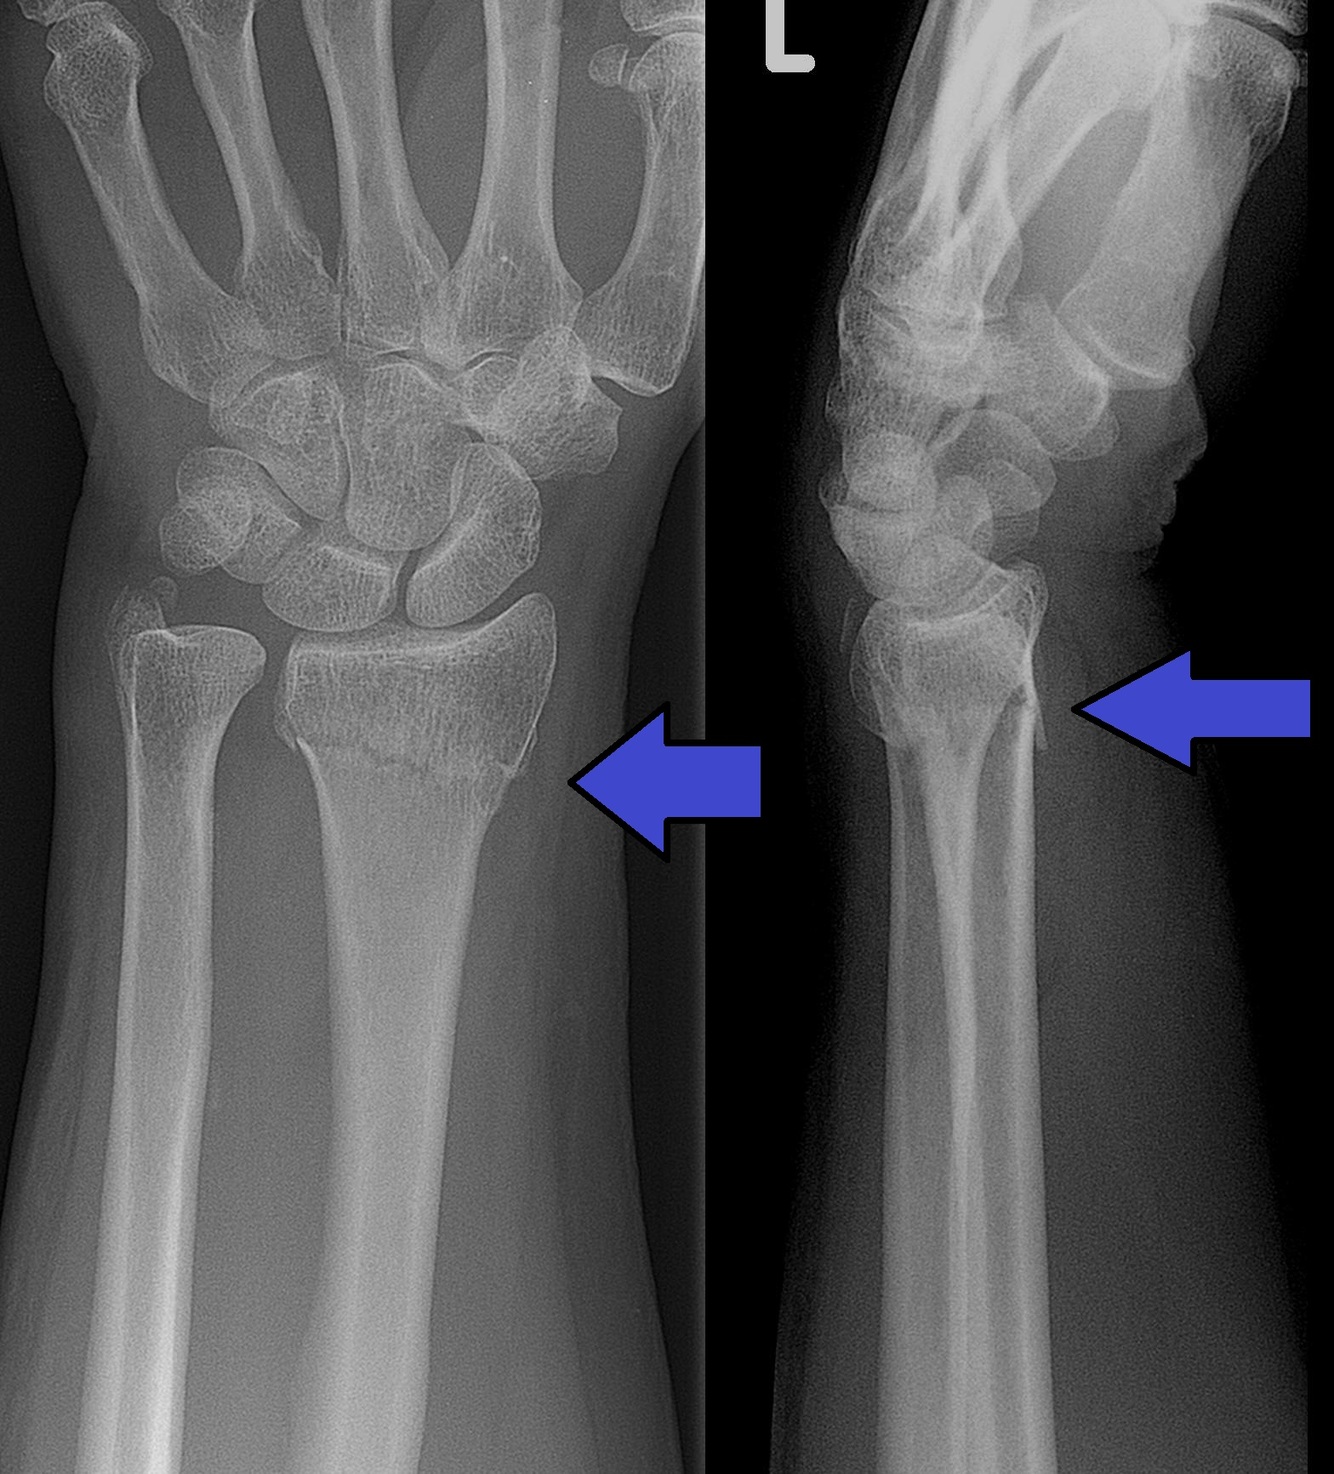

Colle’s fracture

Result of: fall on outstretched hands and extended wrists